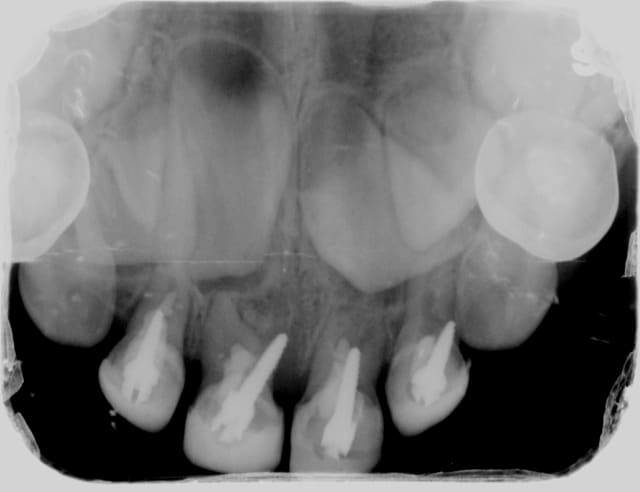

Le screw-post , une technique injustement décriée ...

Regardez ce qu'arrivent à faire de grand professionnels :

Vous êtes médisants, il y en a quand même un qui est dans l'axe !

et si c'était un montage?peut on bidouiller des radios sur le net?

la rhysalyse des racines de dents temporaires est une notion si basique que je n'y crois pas au fait de mettre des screwpost,comme montré par orvietto

et un CD qui se donne la peine de faire des couronnes provisoires sur des anterieures temporaires, ne peut l'ignorer

en ts cas,c'est du jamais vu

Pourvu que les dents définitives suivent les racines et pas les screw posts!

je pense au montage aussi, après réflexion

arriver à faire ça sur un gamin de cet age, en plus, j'y crois pas une seconde.

c'est veridique

Il s'agit d'un cas présenté sur le forum américain Dentaltown dont voici l'URL :

http://www.towniecentral.com/MessageBoard/thread.aspx?s=2&f=136&t=116560&v=1

commentaire du CD qui a posté;

"I just got this patient from another pediatric dentist office. The patient is here for just a routine check-up. What should I recommend. Patient is in no pain and no abscesses present. Work was previously done in OR when she was two years old. She is now four years old. Recommendations?? "

This is an American pediatric dentist fully trained in the US. He is an active member of the AAPD. "